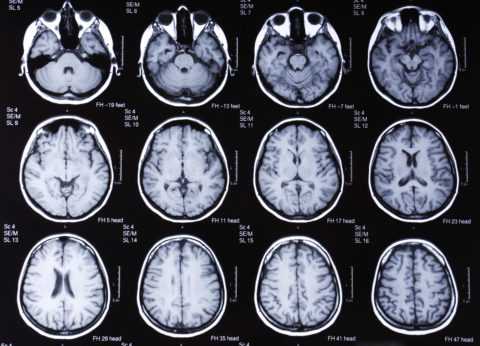

- МРТ, КТ. В начальной стадии изменения не выявляются. На последующих стадиях отмечаются мелкоочаговые диффузные изменения.